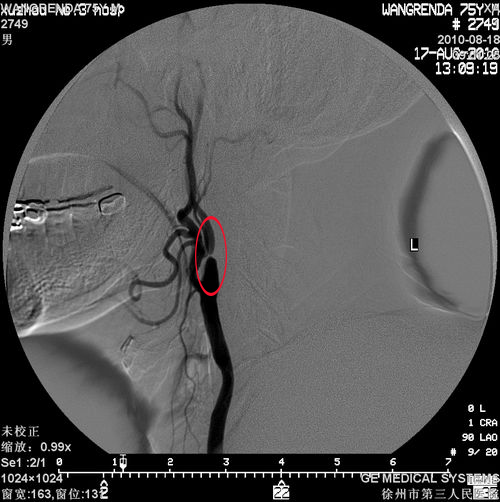

冠状动脉造影(2010-08-17)示:LAD近端局限重度狭窄;左肾动脉轻度狭窄;双颈内动脉狭窄(左侧95%)

右侧颈内动脉